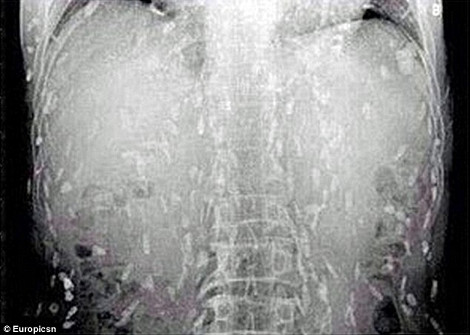

Σύμφωνα με τη Daily Mail, ένας άνδρας επισκέφθηκε τον γιατρό του στην επαρχία Guangdong της ανατολικής Κίνας, έπειτα από στομαχικούς πόνους κι έντονη φαγούρα. Προς μεγάλη του έκπληξη ανακάλυψε ότι στις ακτινογραφίες στις οποίες είχε υποβληθεί, διακρίνονταν εκατοντάδες σκουλήκια να «αλωνίζουν» στο έντερό του και σε άλλα ζωτικά όργανα. Αιτία, σύμφωνα με τους γιατρούς, δεν είναι άλλη από την κατανάλωση χαλασμένου ωμού ψαριού, δηλαδή σούσι. Ο ασθενής εισήχθη στο νοσοκομείο για θεραπεία.

Την ίδια ώρα, έρευνες έχουν δείξει ότι η ολοένα αυξανόμενη προτίμηση σε παγκόσμιο επίπεδο των καταναλωτών στο σούσι, έχει προκαλέσει και την αύξηση των κρουσμάτων σοβαρής δηλητηρίασης και άλλων παρασιτικών μολύνσεων. Συνήθως, εκείνοι που προσβάλλονται συχνότερα είναι οι καταναλωτές που προτιμούν τον ωμό σολομό.